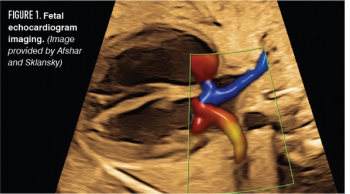

A review of the risks, benefits, and indications for appropriate referral of fetal echocardiography